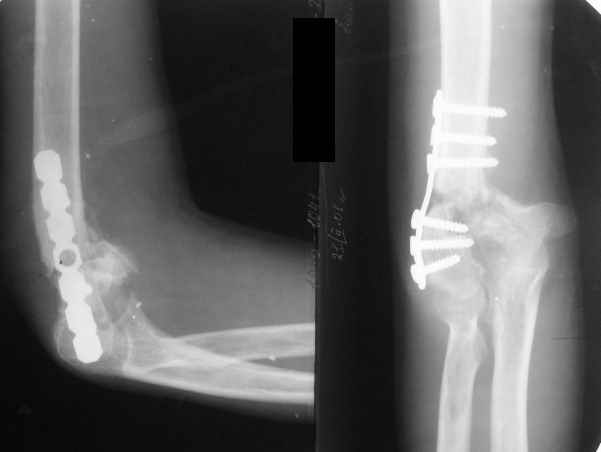

The recent x rays show established Non union with poor quality bone in the distal fragement. The joint is also appearing degenerate. In view of the multiple failed reconstructive surgeries, an Elbow replacement would seem reasonable.

However it would have to be a fully constrained one as there would be missing bone stock.